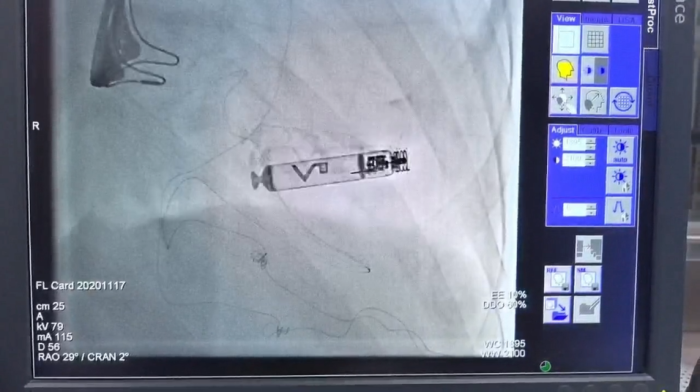

无导线起搏器植入后效果图

12月2日,在局部麻醉下,邓英松副主任医师带领团队操作熟练,各人员配合有条不紊,成功将无导线起搏器植入患者体内。手术完成后,起搏器参数完美,患者感觉良好,甚至察觉不到起搏器的存在。术后,罗先生恢复情况良好,各项生命体征平稳,已经转入普通病房进行后续观察治疗。